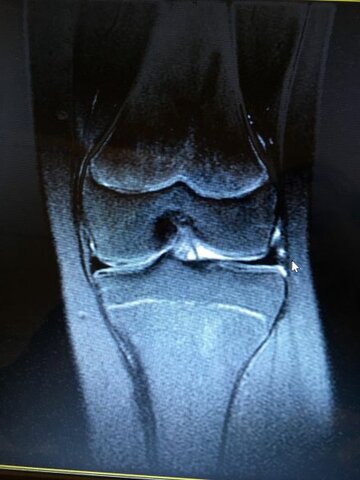

• Menisc Trencat

Menisc Trencat

Jo em vaig encara fent un partit de Bàsquet. El menisc és un tros de cartílag en forma de C a l'articulació del genoll. El cartílag del menisc és un teixit fort, però flexible que actua com un amortidor entre els extrems dels ossos en una articulació.